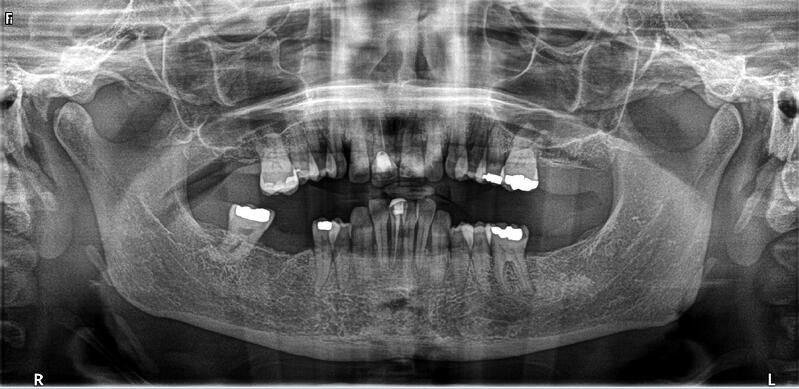

術(shù)前診斷

治 療方案